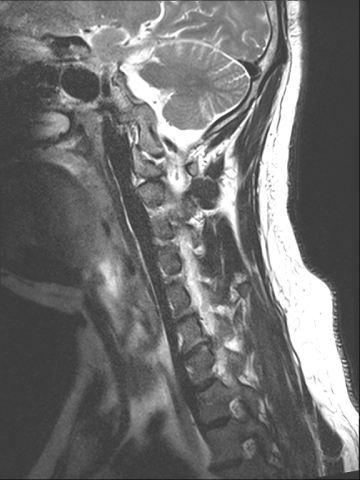

목디스크 수술 치료

2019.05.25

2022.09.13

2022.11.10

2022.11.16